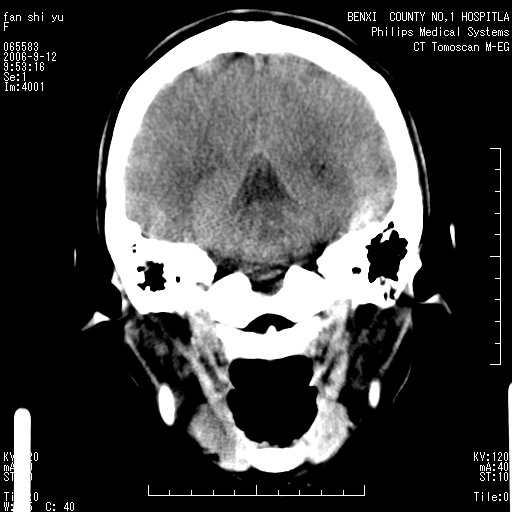

标题: CT4607:看看这个头颅冠状位。

女,22岁,自觉头顶部质硬包块.

巨大蛛网膜粒压迹。

巨大蛛网膜粒压迹